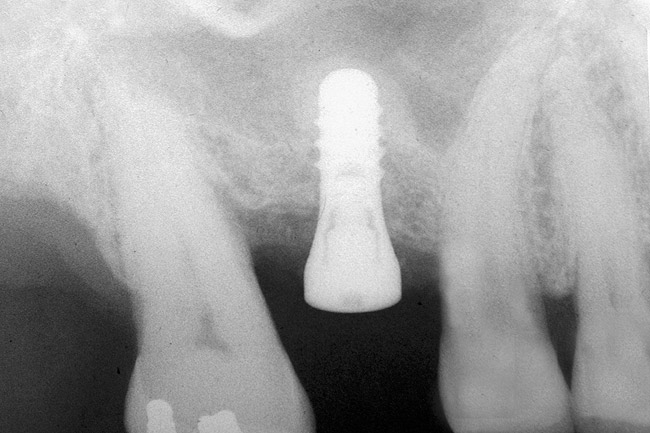

If the final osteotome employed was 3.5 mm, the size of the implant that can be placed should be 4.1-mm diameter or larger depending on the width of the ridge. Several factors should be considered when selecting the width of the inserted implant. If the height is relatively short (eg, 8 mm), a wider implant such as a 4.8-mm diameter will provide 30% more surface area than a 4.1-mm diameter implant (Figure 5).24 In addition, the wider implant will provide additional stability, especially if hand use of osteotomes caused some irregularities of the osteotomy site.

Figure 5  Insertion of a 4.8-mm implant, which fit snugly and increased the surface area for future osseointegration.

Figure 5